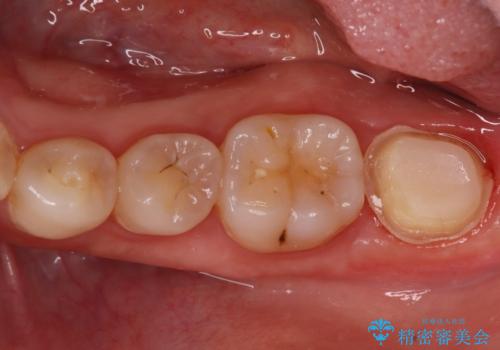

- 昨日からのズキズキとした激しい痛みを主訴にご来院されました。レントゲンおよび歯髄診察の結果、不可逆性の歯髄炎(歯の神経の重度の炎症)と診断。歯を残すことを第一に、まず痛みの原因である神経を取り除く根管治療を提案しました。また、虫歯が歯肉の下まで深く進行していたため、根管治療後に歯周外科処置を行い、最終的に精密なセラミッククラウンで修復する、総合的な治療計画を立案しました。

治療はまず、根管治療から始め、感染した神経を徹底的に除去することで、痛みをすぐに解消しました。再発を防ぐため、ラバーダムや顕微鏡を使って、根管内を丁寧に、そして精密に処置しました。次に、深い部分の虫歯を確実に治療するため、歯周外科処置を行い、治療しやすい環境を整えました。最後に、機能と見た目に優れたセラミッククラウンを作製・装着。根管治療から外科処置、審美修復までを一貫して行うことで、再発リスクの低い、長期的に安定して使える奥歯を取り戻していただけました。